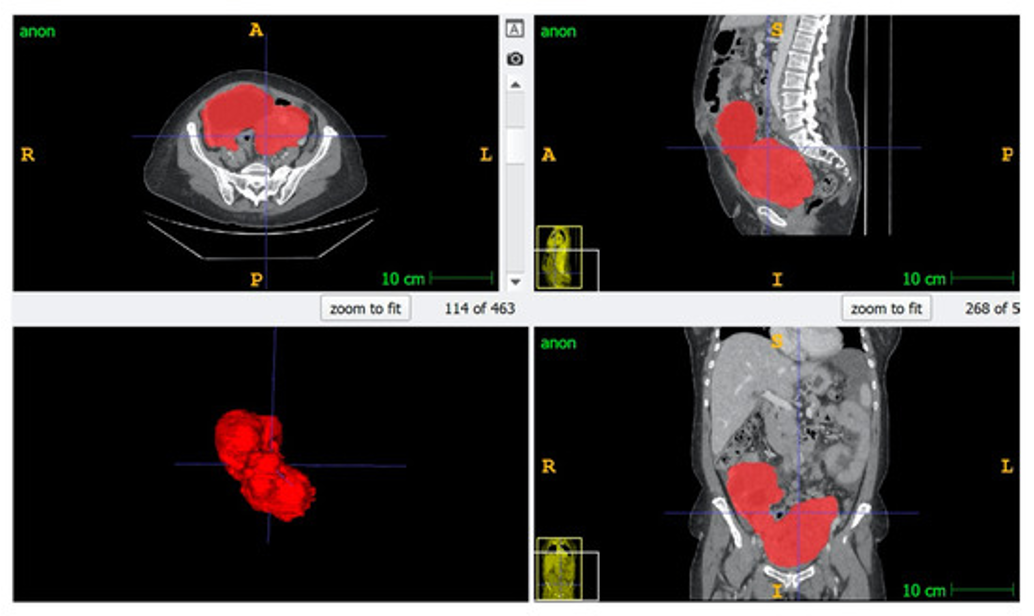

At the PINKCC Lab, our research pushes the boundaries of cross-sectional oncologic imaging to transform how cancer is detected, characterized, and treated. In partnership with Siemens Healthineers, we are developing next-generation MRI sequences that go beyond anatomy to capture tumor biology in vivo—including hypoxia and pH-sensitive CEST imaging (Chemical Exchange Saturation Transfer), which detects subtle proton exchanges between metabolites and water to map tissue acidity as a biomarker of aggressiveness. We also advance IVIM (Intravoxel Incoherent Motion)–derived parameters, separating true diffusion from microvascular perfusion, to non-invasively monitor treatment response and personalize therapy early in the course of care. Complementing this physiological imaging, our team designs AI-driven segmentation algorithms that precisely delineate tumors and peritoneal disease, providing surgeons with actionable 3D roadmaps to improve resectability, reduce morbidity, and ultimately elevate patient outcomes. Together, these innovations redefine medical imaging as a powerful decision-making tool—not just to see cancer, but to understand it.

At the PINKCC Lab, we transform medical images into quantitative biomarkers that reveal tumor biology beyond what the human eye can see. Using high-quality cross-sectional imaging and precise manual and AI-based segmentation, we extract thousands of radiomic features describing tumor shape, texture, heterogeneity, and microenvironment. These data are then integrated with clinical, pathological, and genomic information to develop predictive models that can anticipate treatment response, assess resectability, and support truly personalized cancer care. Our radiomics program is applied at scale across ovarian, rectal, and peritoneal disease, with large curated cohorts and external validation to ensure robustness and clinical translation.